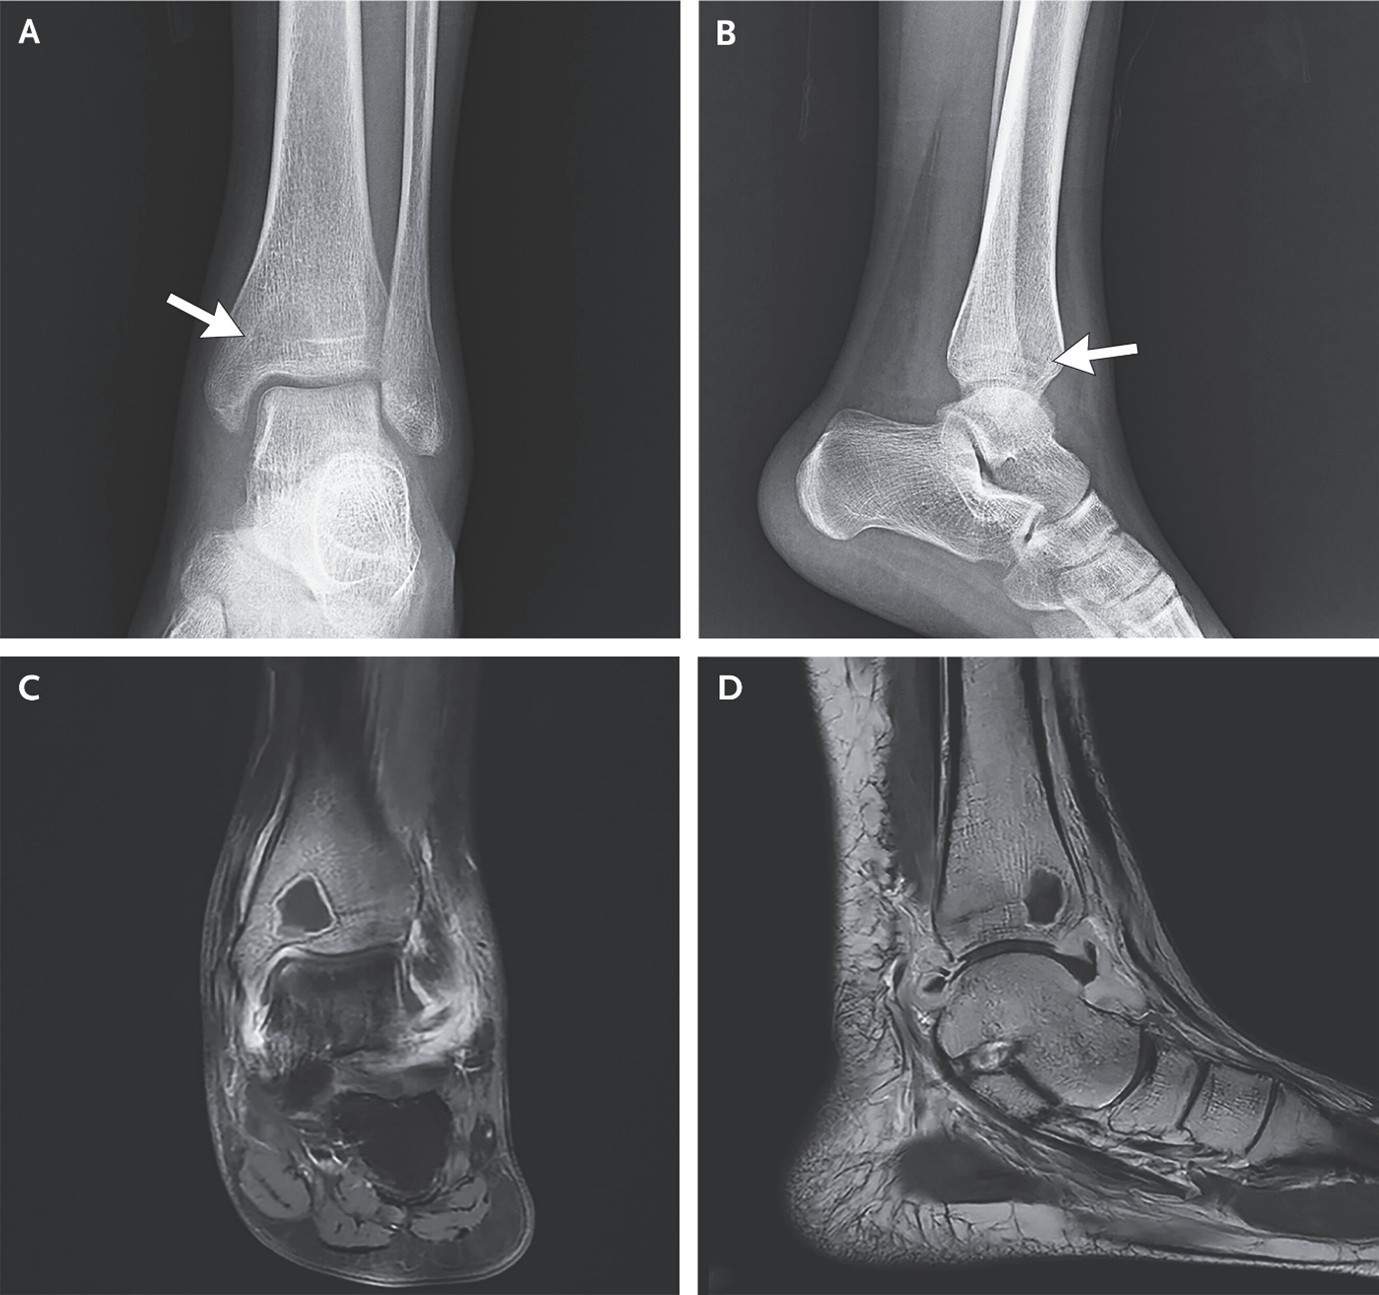

(9). Intraosseous Abscess from Subacute Osteomyelitis

Haijian Li, et al, Published April 11, 2026,N Engl J Med 2026;394:1529,DOI: 10.1056/NEJMicm2514540,VOL. 394 NO. 15

A 16-year-old girl presented with 1 month of ankle pain and 11 days of fever. Radiographs showed an ill-defined, radiolucent distal tibial lesion; on MRI, the lesion was hypointense and surrounded by a hyperintense sclerotic rim.